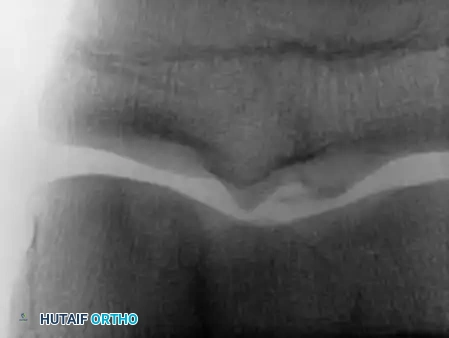

Osteochondritis dissecans (OCD) of the ankle primarily affects the talar dome. The natural history of this lesion in children with open physes is highly favorable compared to adult populations.

Natural History and Imaging

Bauer et al., in a long-term follow-up study (≥ 20 years) of 30 children with ankle osteochondritis, found that only one patient developed severe osteoarthritis. The vast majority experienced complete healing with only minor residual radiographic changes. This is in stark contrast to osteochondritis of the knee, where secondary osteoarthritis is a frequent complication.

Radiographic and MRI evaluation of osteochondral lesions of the talar dome, demonstrating subchondral separation and surrounding edema.